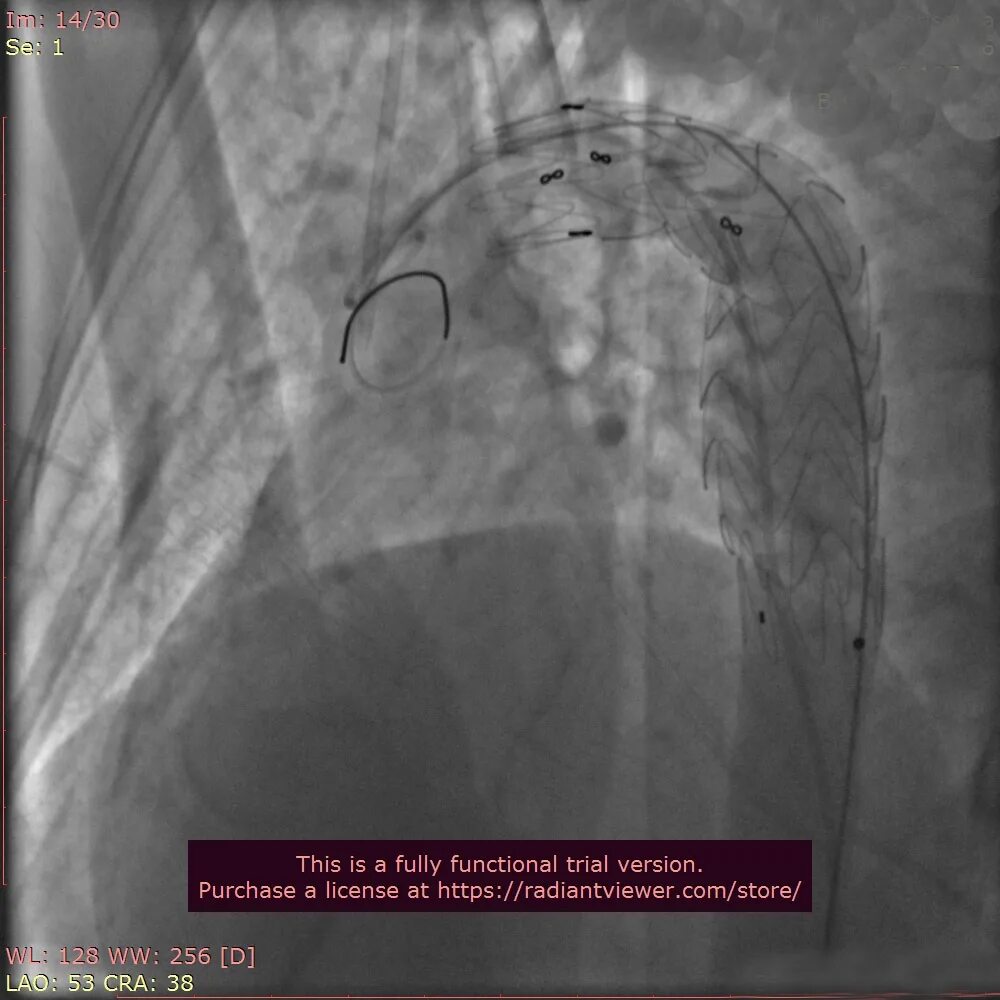

От чего бывает разрыв аорты